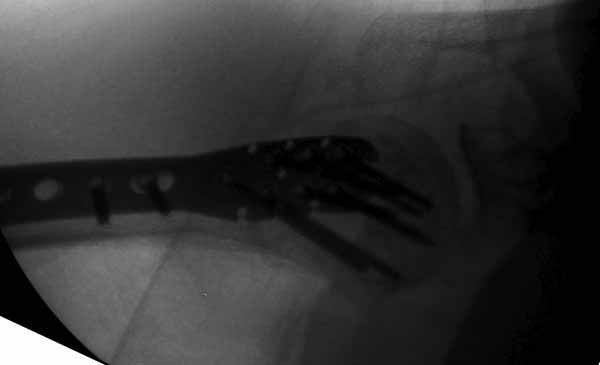

Уважаемы коллеги! Прошу помочь определиться с тактикой лечения пациентки. В феврале в отделение поступила пациентка с оскольчатым переломо-вывихом головки плечевой кости. Выполнена операция -остеосинтез блокируемой пластиной. Костная пластика не производилась. На контрольных рентгенограммах остается сублюксация головки и смещение большого бугорка. Интраоперационно бугорок подшивался с помощью лавсановых нитей. Послеоперационно: ношение косыночной повязки и пассивные движения в плечевом суставе в течение 2,5-х месяцев без особенностей. Через 2,5 месяца при попытке выполнения пассивно-активных движений произошел передний вывих плечевой кости.Вся реабилитация производилась по месту жительства. Таким образом существование вывиха в течение 1 месяца. Боли не беспокоят. Нейрососудистых нарушений в конечности нет. Что вы можете посоветовать: пластику, эндопротез, артродез? Заранее спасибо.

мне кажется ,что на послеоперационном снимке, также имеется сублюксация головки.сколько годов пациентке?

Уважаемый коллега. На мой взгляд имеющаяся дислокация головки обусловлена на мой взгляд имеющейся у пациента обширной травмой ротаторного аппарата. В пользу данной точки зрения могу привести следующее: на представленных Вами рентгенограммах хорошо заметен отрыв большого бугорка со смещением отломков который как известно является точкой прикрепления коротких наружных ротаторов плеча. Последующая миграция данного фрагмента и неполноценная репозиция его при первичном остеосинтезе с нестабильной фиксацией на мой взгляд и обусловили создавшуюся ситуацию. то что пациента не беспокоят боли позволю подвергнуть сомнению поскольку сам занимаюсь хирургией плеча и с подобными ситуациями сталкивался неоднократно. На мой взгляд в настоящее время целесообразно проведение повторного оперативного вмешательства с адекватным восстановлением ротаторного аппарата, поскольку дальнейшее затягивание сложившейся ситуации уменьшает шанс на успех данного вмешательства.

Набор мелких снимков не отражает истинную картину суставной поверхности лопатки, а также качество репозиции головки плеча. Необходимо доказать аксиальным снимком наличие покрытия головки. Правильная маркировка на рентген снимках и соответствие с выставленным диагнозом гарантирует от ошибок со стороной во время операции!

Здесь результат похожего случая, больная 87 лет, отягощенная сердечными делами и два года назад установка pacemaker и нескольких стентов. На третий день, сегодня утром сделали операцию. Послеоперационный псевдовывих связанный с релаксацией мышц и общим обезболиванием.